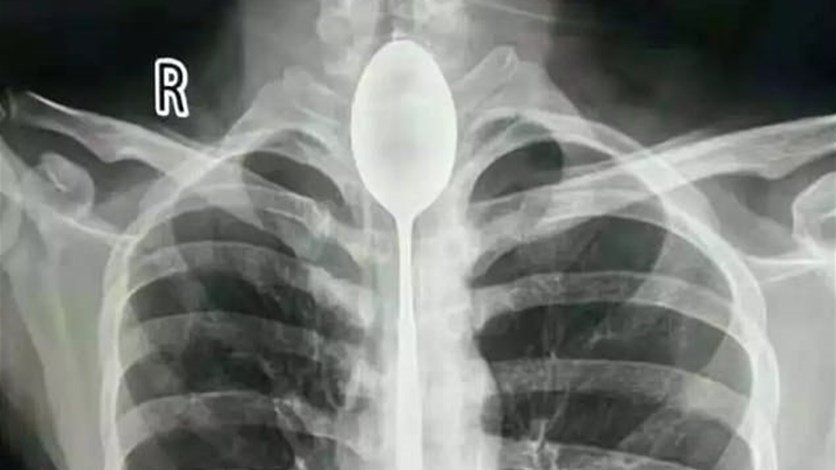

| صيني يبتلع ملعقة |

قرر رجل صيني التوجه إلى المستشفى لإخراج ملعقة معدنية ابتلعها بعدما تحدوه أصدقائه على ذلك قبل نحو عام. فقد تحدى الشاب، 26 عاماً، أصدقاءه بأنه يمكنه ابتلاع ملعقة، وإعادة... |